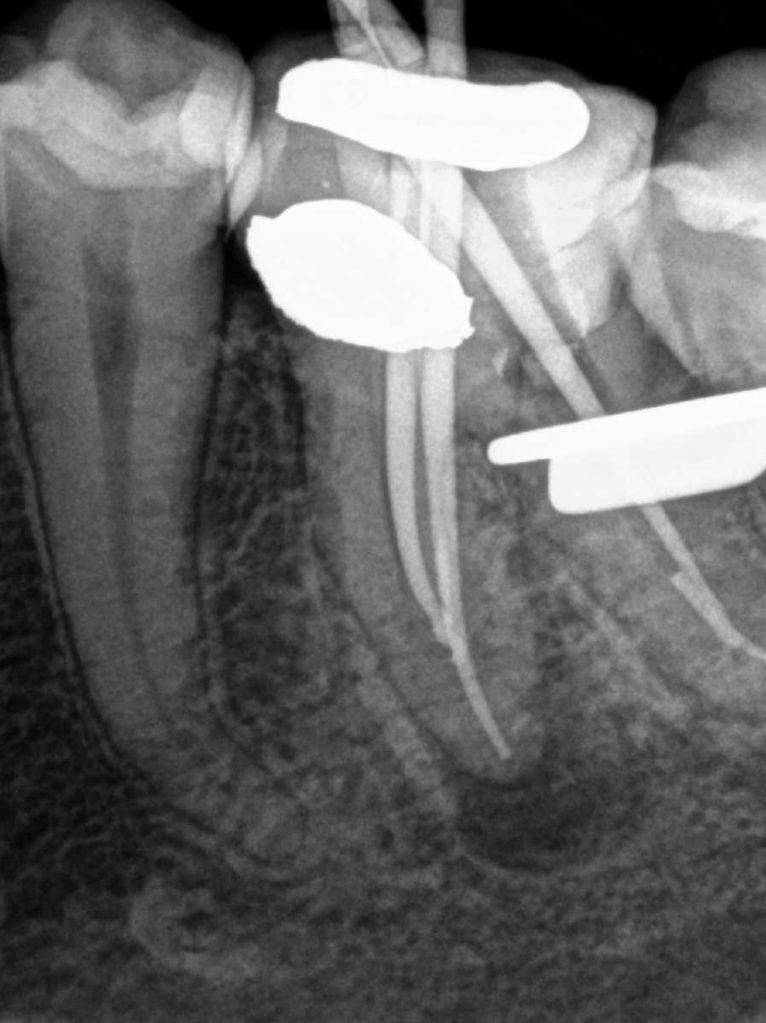

Retratamiento Molar Superior

Retratamiento Primer Molar Superior

Retratamiento, Localización 4o Conducto